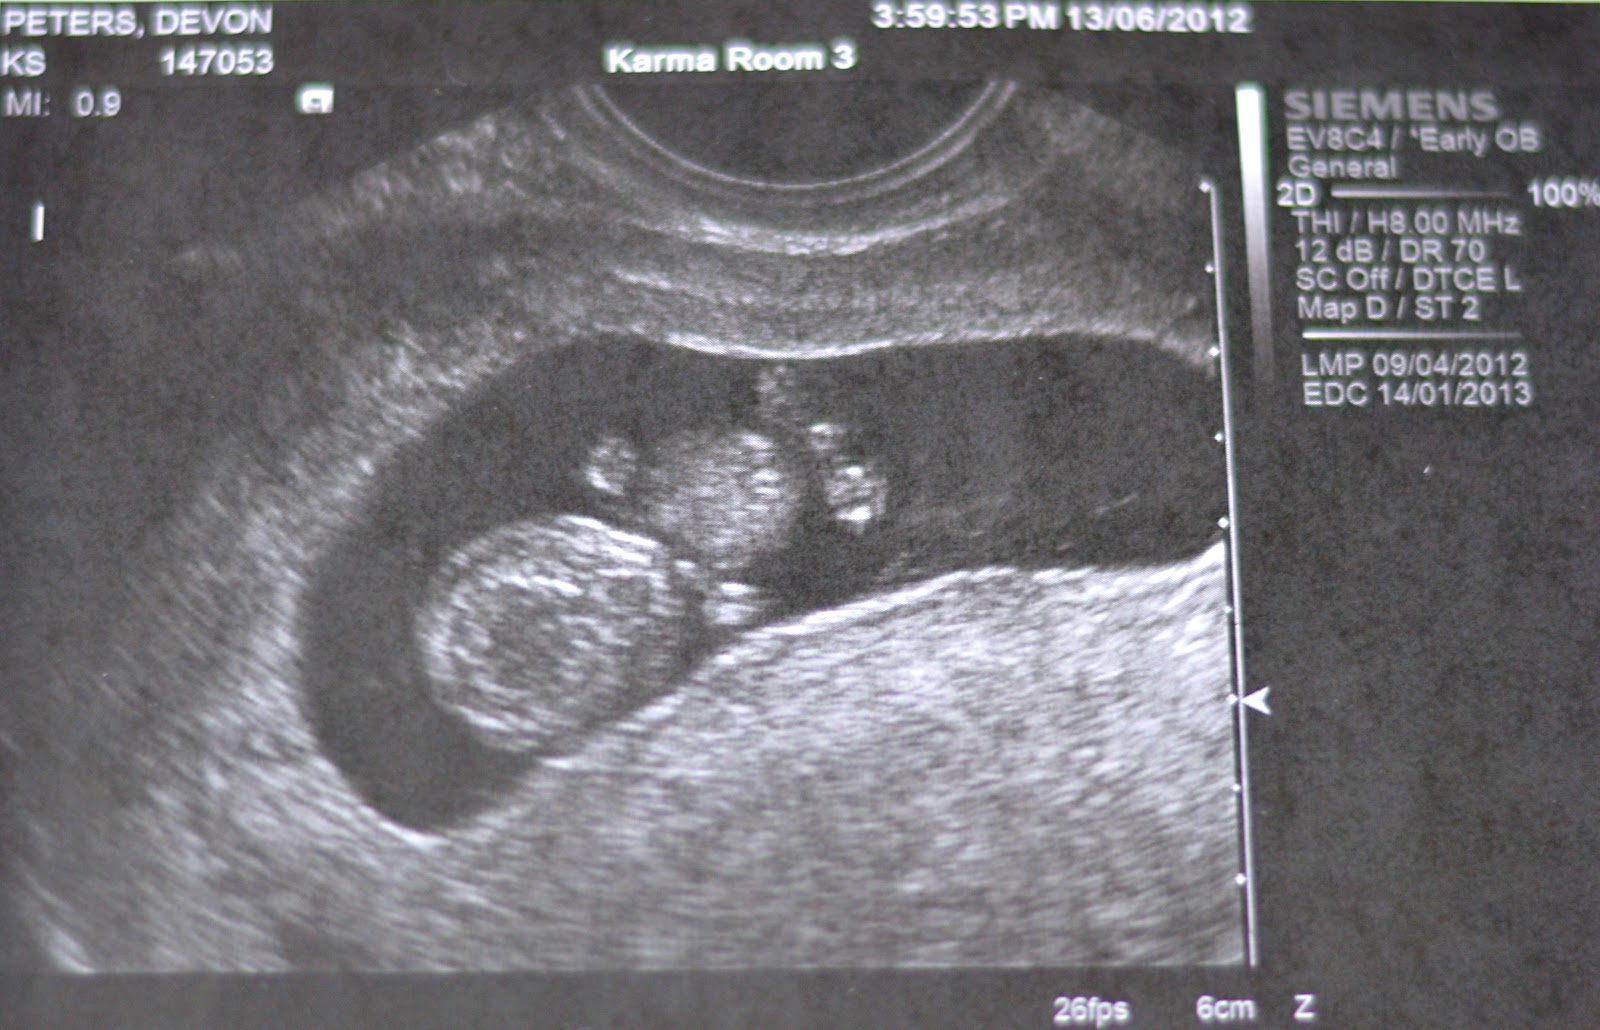

How to detect ovulation on ultrasound. Possible to detect ovulation in more than 80 of cycles studied. To confirm ovulation serum progesterone or its metabolite in urine can be measured. The gestational sac can be seen around cycle days 32 35 which is about 18 21 days after ovulation fertilization. Numerous meth ods based upon the secretion of pituitary and ovar received march 25 1980.

The first scanning is appointed after the end of menstruation about a week before the expected ovulation and then repeated every 2 3 days. Fertil steril34 99 1980 a simple reliable method is needed to predict and detect ovulation in women. After ovulation the dominant follicle turns into a corpus luteum and begins to secrete progesterone. However sometimes it can take a couple of days longer to see the gestational sac on transvaginal ultrasound.

This technique was found to be quick inexpensive and efficient. However by measuring the maximal diameter of the follicle and observing the morphologic changes within the ovary from follicle to corpus luteum it was possible to detect. This common fertility test for women can be performed in two ways. It requires several visits to the ultrasound room during the cycle.

Researchers have compared ultrasound results to commonly used methods of ovulation tracking. Urine test kits to measure luteininzing hormone lh levels. Ultrasound monitoring or folliculometry is the most reliable almost 100 way to detect ovulation. Accepted april 24 1980.